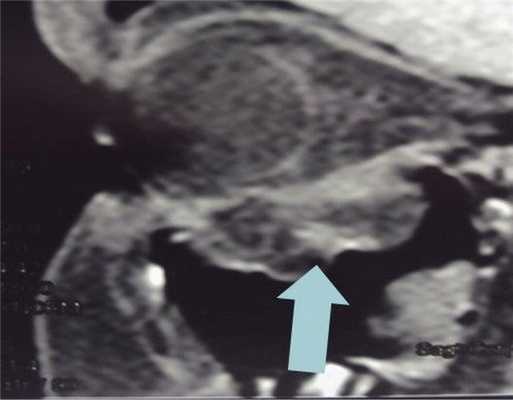

Пациент Ш., 18 лет, обратился в нейрохирургическое отделение стационара медико-санитарной части «Нефтяник» с жалобами на диплопию, сохраняющуюся в течение 2 нед после тупой травмы глазницы справа. На МСКТ околоносовых пазух и орбиты справа определяется дефект верхней стенки ВЧП с пролабированием параорбитальной жировой клетчатки в пазуху (рис. 7). Рис. 7. Пациент Ш., 18 лет. МСКТ. Посттравматический дефект нижней стенки глазницы. Пролабирование параорбитальной клетчатки в просвет ВЧП (указано стрелкой). Prolapse of the paraorbital adipose tissue into the maxillary sinus lumen (indicated by he arrow).

На 2-е сутки была выполнена контрольная МСКТ, которая подтвердила стабильное положение нетканной титановой конструкции и отсутствие реактивных изменений слизистой оболочки ВЧП. Произведено снятие косметического шва на нижнем веке, зрачки на одном уровне. Пациент отмечает отсутствие диплопии.